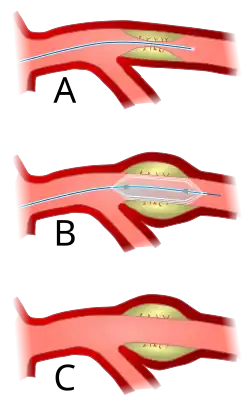

A vascular surgeon may diagnose PAD using a combination of history, physical exam and medical imaging. Medical imaging may include ankle-brachial index, doppler ultrasonography and computed tomography angiography, among others. Treatments are individualized and may include medical therapy, endovascular intervention or open surgical options including angioplasty, stenting, atherectomy, endarterectomy and vascular bypass, among others.

Angioplasty (pictured) and stenting are two endovascular treatments employed by the vascular surgeon.

Angioplasty (pictured) and stenting are two endovascular treatments employed by the vascular surgeon.